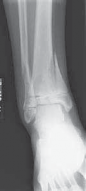

A B CTECH FIG 1•

Surgical approach to a medially gapped fracture.

A.

This AP radiograph demonstrates a medially gapped Salter-Harris type II abduction-type fracture.

B.

A medial approach is used to obtain open reduction of this fracture.

C.

This operative photograph highlights the periosteum interposed in the physeal fracture, which was extracted to obtain anatomic reduction and prevent medial gapping.